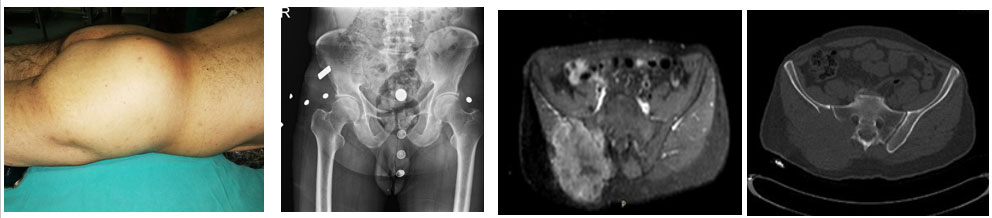

Ameliyat Öncesi: Klinik olarak şişlik, röntgende ise yeniklik (lizis), MR ve tomografide ağırlıklı olarak leğen kemiğinin arkasında ciddi yıkıma neden olan, sakrumu etkileyen ve büyük bir tümör dokusunun eşlik ettiği metastaz varlığı görülmekte